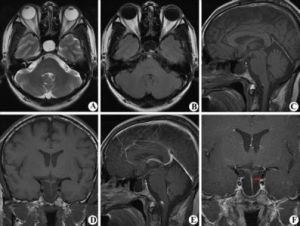

空蝶鞍綜合徵系指蛛網膜下腔伸展至蝶鞍內,使垂體縮小、壓扁,蝶鞍擴大,可引起一定的臨床症狀。可為原發性,也可繼發於垂體瘤手術或放療後。

疾病分類 發病原因 病理生理 臨床表現 診斷及鑑別診斷空鞍綜合徵(emptysellasyndrome)是指蛛網膜下腔疝入垂體窩內,使垂體受壓變形及蝶鞍擴大引起的1組綜合徵。女性病人多見,占80%~90%。...

疾病描述 症狀體徵 疾病病因 病理生理 診斷檢查空鞍綜合徵(empty sella syndrome)是指蛛網膜下腔疝入垂體窩內,使垂體受壓變形及蝶鞍擴大引起的1組綜合徵。空鞍綜合徵一詞最早於1949...

臨床套用空鞍綜合徵是指蛛網膜下腔疝入垂體窩內,使垂體受壓變形及蝶鞍擴大引起的1組綜合徵。空鞍綜合徵一詞最早於1949年由Sheehan和Summers曾用於描述...